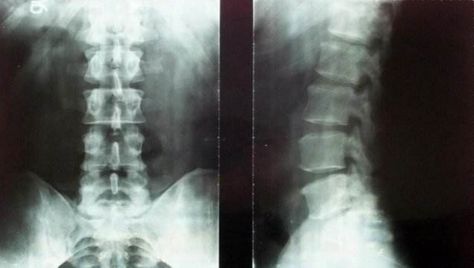

正常腰椎正侧位片

强直性脊柱炎腰椎正侧位片